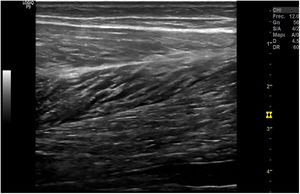

El músculo sano, ecográficamente, presenta una ecogenicidad inferior a la del tejido celular subcutáneo y una disposición de finas líneas paralelas ecogénicas, múltiples, en cortes longitudinales, en «pluma de ave» (fig. 1), y aspecto reticular en corte transversal «aspecto moteado» (fig. 2), rodeados por la fascia hiperecogénica y en su interior la unión miotendinosa también hiperecogénica4. En ecografía se describen 4 grados de lesión muscular propuestos por Peetrons en 20027 (tabla 2).

| GRADO 0: Ecografía negativa a pesar de clínica sugestiva Grado 1: Área sutil mal definida hiperecoica o hipoecoica sin defecto fibrilar objetivado o inflamación de la aponeurosis (fig. 3). Corresponde a una elongación con menos del 5% del músculo involucrado. El dolor puede ser intenso pero muy inespecífico Grado 2: Discontinuidad parcial de las fibras (fig. 4). Afecta entre el 5 y 50% del volumen muscular o del diámetro de la sección transversal. Defecto hipoecoico o anecoico dentro de las fibras musculares. Una suave presión con el transductor objetiva fragmentos desgarrados musculares que flotan en un fluido serohemático en «badajo de campana» Grado 3: Discontinuidad total de las fibras (fig. 5). Retracción completa del músculo. Lesiones clínicamente evidentes ya que el vientre retraído forma una masa muscular y un hachazo palpable en el músculo |